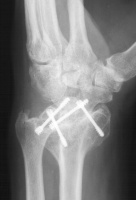

Three months postop :

Radioscapholunate fusion is a treatment option for radiocarpal arthritis following distal radius fracture or associated with rheumatoid arthritis. Range of motion is usually less than half of normal following this procedure. Technical modifications to improve range of motion include distal scaphoid excision, or as in this case, triquetrum excision and excision of distal ulnar articular surface to manage ulnolunate abutment. There are a variety of fixation techniques. In this case, crossed Herbert screws were used: dorsal carpal bone to palmar radius and dorsal radius to palmar carpal bone.